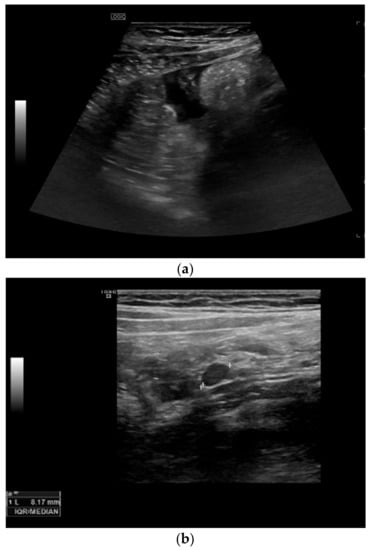

Among the extraintestinal features of active CD, we can detect the presence of free fluid in the peritoneal cavity, enlarged mesenteric lymph nodes, and fibro-fatty proliferation (echogenic peri-enteric fat). Detection of free fluid close to the affected bowel segments is a non-specific but common finding. Enlarged mesenteric loco-regional lymph nodes are not specific of CD and can be present in other abdominal pathologies, but they are correlated with young age, early disease or disease with shorter duration, and with the presence of fistulae and abscesses [,]. Fibro-fatty proliferation or echogenic peri-enteric fat looks like hyperechoic tissue surrounding the diseased bowel and can be observed in patients with long-standing CD (see Figure 4).

Figure 4.

Extraintestinal ultrasonographic findings. (a) Presence of free fluid. (b) Detection of a lymph node and presence of fibro-fatty proliferation (echogenic peri-enteric fat).

Depending of the CD phenotype, different ultrasonographic characteristics can be identified. The presence of ulcers can be visualized as depressions in the mucosal layer. Strictures are characterized by wall thickening with a narrowed lumen, with or without a dilatation of the proximal loop (pre-stenotic dilatation) (see Figure 5). The fistulae are seen as hypoechoic peri-intestinal areas with diameter < 2 cm with or without internal gaseous artifacts. Abdominal abscesses are seen as hypo-anechoic lesions containing fluid and gaseous artifacts, posterior enhancement, irregular margins sometimes within hypertrophic mesentery, without vascular signals at color Doppler (see Figure 6). An inflammatory mass is seen as an irregular hypoechogenic lesion, with vascular signals at color Doppler.

Figure 6.

Detection of complications: fistulae and abscesses: (a) The fistulae are seen as hypoechoic peri-intestinal areas with a diameter <2 cm with or without internal gaseous artifacts. (b) Abdominal abscesses are seen as hypo-anechoic lesions containing fluid and gaseous artifacts, posterior enhancement, irregular margins sometimes within fibro-fatty proliferation, without vascular signals in color Doppler.